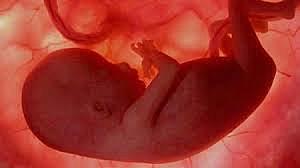

• Semana 3

17

Semana 3

El cerebro, el corazón y la médula espinal comienzan a desarrollarse

o el tubo digestivo comienza a desarrollarse.

• Semana 4

18

Semana 4

se aprecian los dos primeros arcos faríngeos.

Los esbozos de los miembros superiores se reconocen hacia el día 26 y 27 como pequeñas tumefacciones en las paredes corporales ventrolaterales.

Las fositas óticas, los primordios de los oídos internos, también se ven